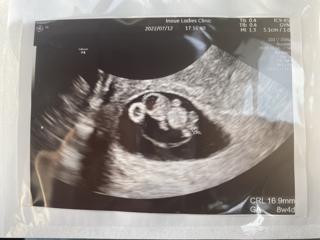

写真:8w4d:マカロンさん

先週までそら豆みたいな二頭身だったのに手足がくっきりして10w2dほどのビッグサイズでしたが順調という事でした♡

赤ちゃんのサイズが16.9mm

頭ぽい所体っぽいところ手足っぽいところがはっきり見えて、しかも心臓もピコピコ動いてるのご見れて感動しました!

8w4dで赤ちゃん1.67㎝!出産予定日10月1日って言われましたー! 1週間前まで丸っこかったのに、今日は手足がはえてて人間らしくなってて、感動しました!心臓もちゃんと動いてて安心。